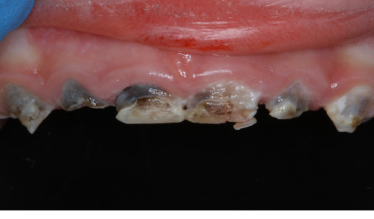

Впервые в Екатеринбурге «Мегадента Клиник» представляет технологию восстановления разрушенных передних зубов эстетичными коронками. В чем преимущества метода и когда он необходим? Бутылочный кариес — одно из самых...